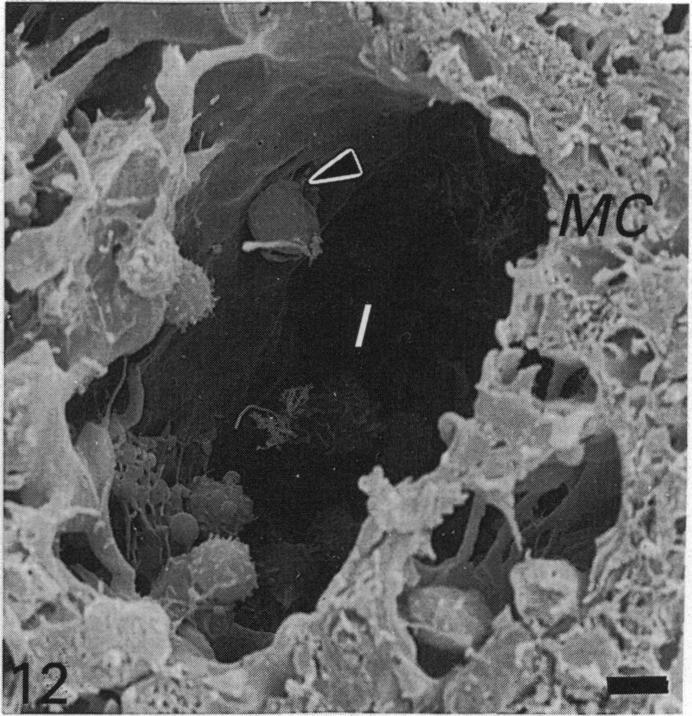

Lymphatic drainage from the wall of the distal small intestine, important especially in young sheep as a major site of gut-associated lymphoid tissue, begins with a series of longitudinally oriented subserosal vessels. These vessels convey lymph to the mesenteric border of the intestinal wall and unite to form larger vessels which course through the mesentery to the mesenteric lymph nodes. These nodes lie towards the periphery of a broad, fan-shaped mesentery, adjacent to major arteries and veins. Mesenteric vessels convey lymph from the jejunum and part of the proximal ileum to the jejunal nodes. Lymph from most of the ileum is conveyed to caecal nodes. The larger mesenteric lymphatics have well formed smooth muscle and connective tissue layers surrounding the endothelium. They are often adjacent to, but rarely within, the connective tissue band anchoring the major arteries and veins to one or both lamellae of mesentery. Few anastomoses occur between vessels from opposing sides of the gut wall or the mesentery. Afferent lymphatics enter the subcapsular and trabecular sinuses of the nodes over most surfaces apart from the hilar region. Lymph flows through cortical tissue to the medulla, which occupies most of the node. In the medulla, sinuses occur within medullary cords as well as between them. Initial efferent lymphatics occur throughout medullary tissue. Efferent vessels emerge at a hilus then coalesce and drain into the jejunal or ileal trunk. The hilus of the node varies from a flat, poorly defined area on the lesser curvature, to a depression or groove. The latter commonly occurs in elongated jejunal nodes.(ABSTRACT TRUNCATED AT 250 WORDS)